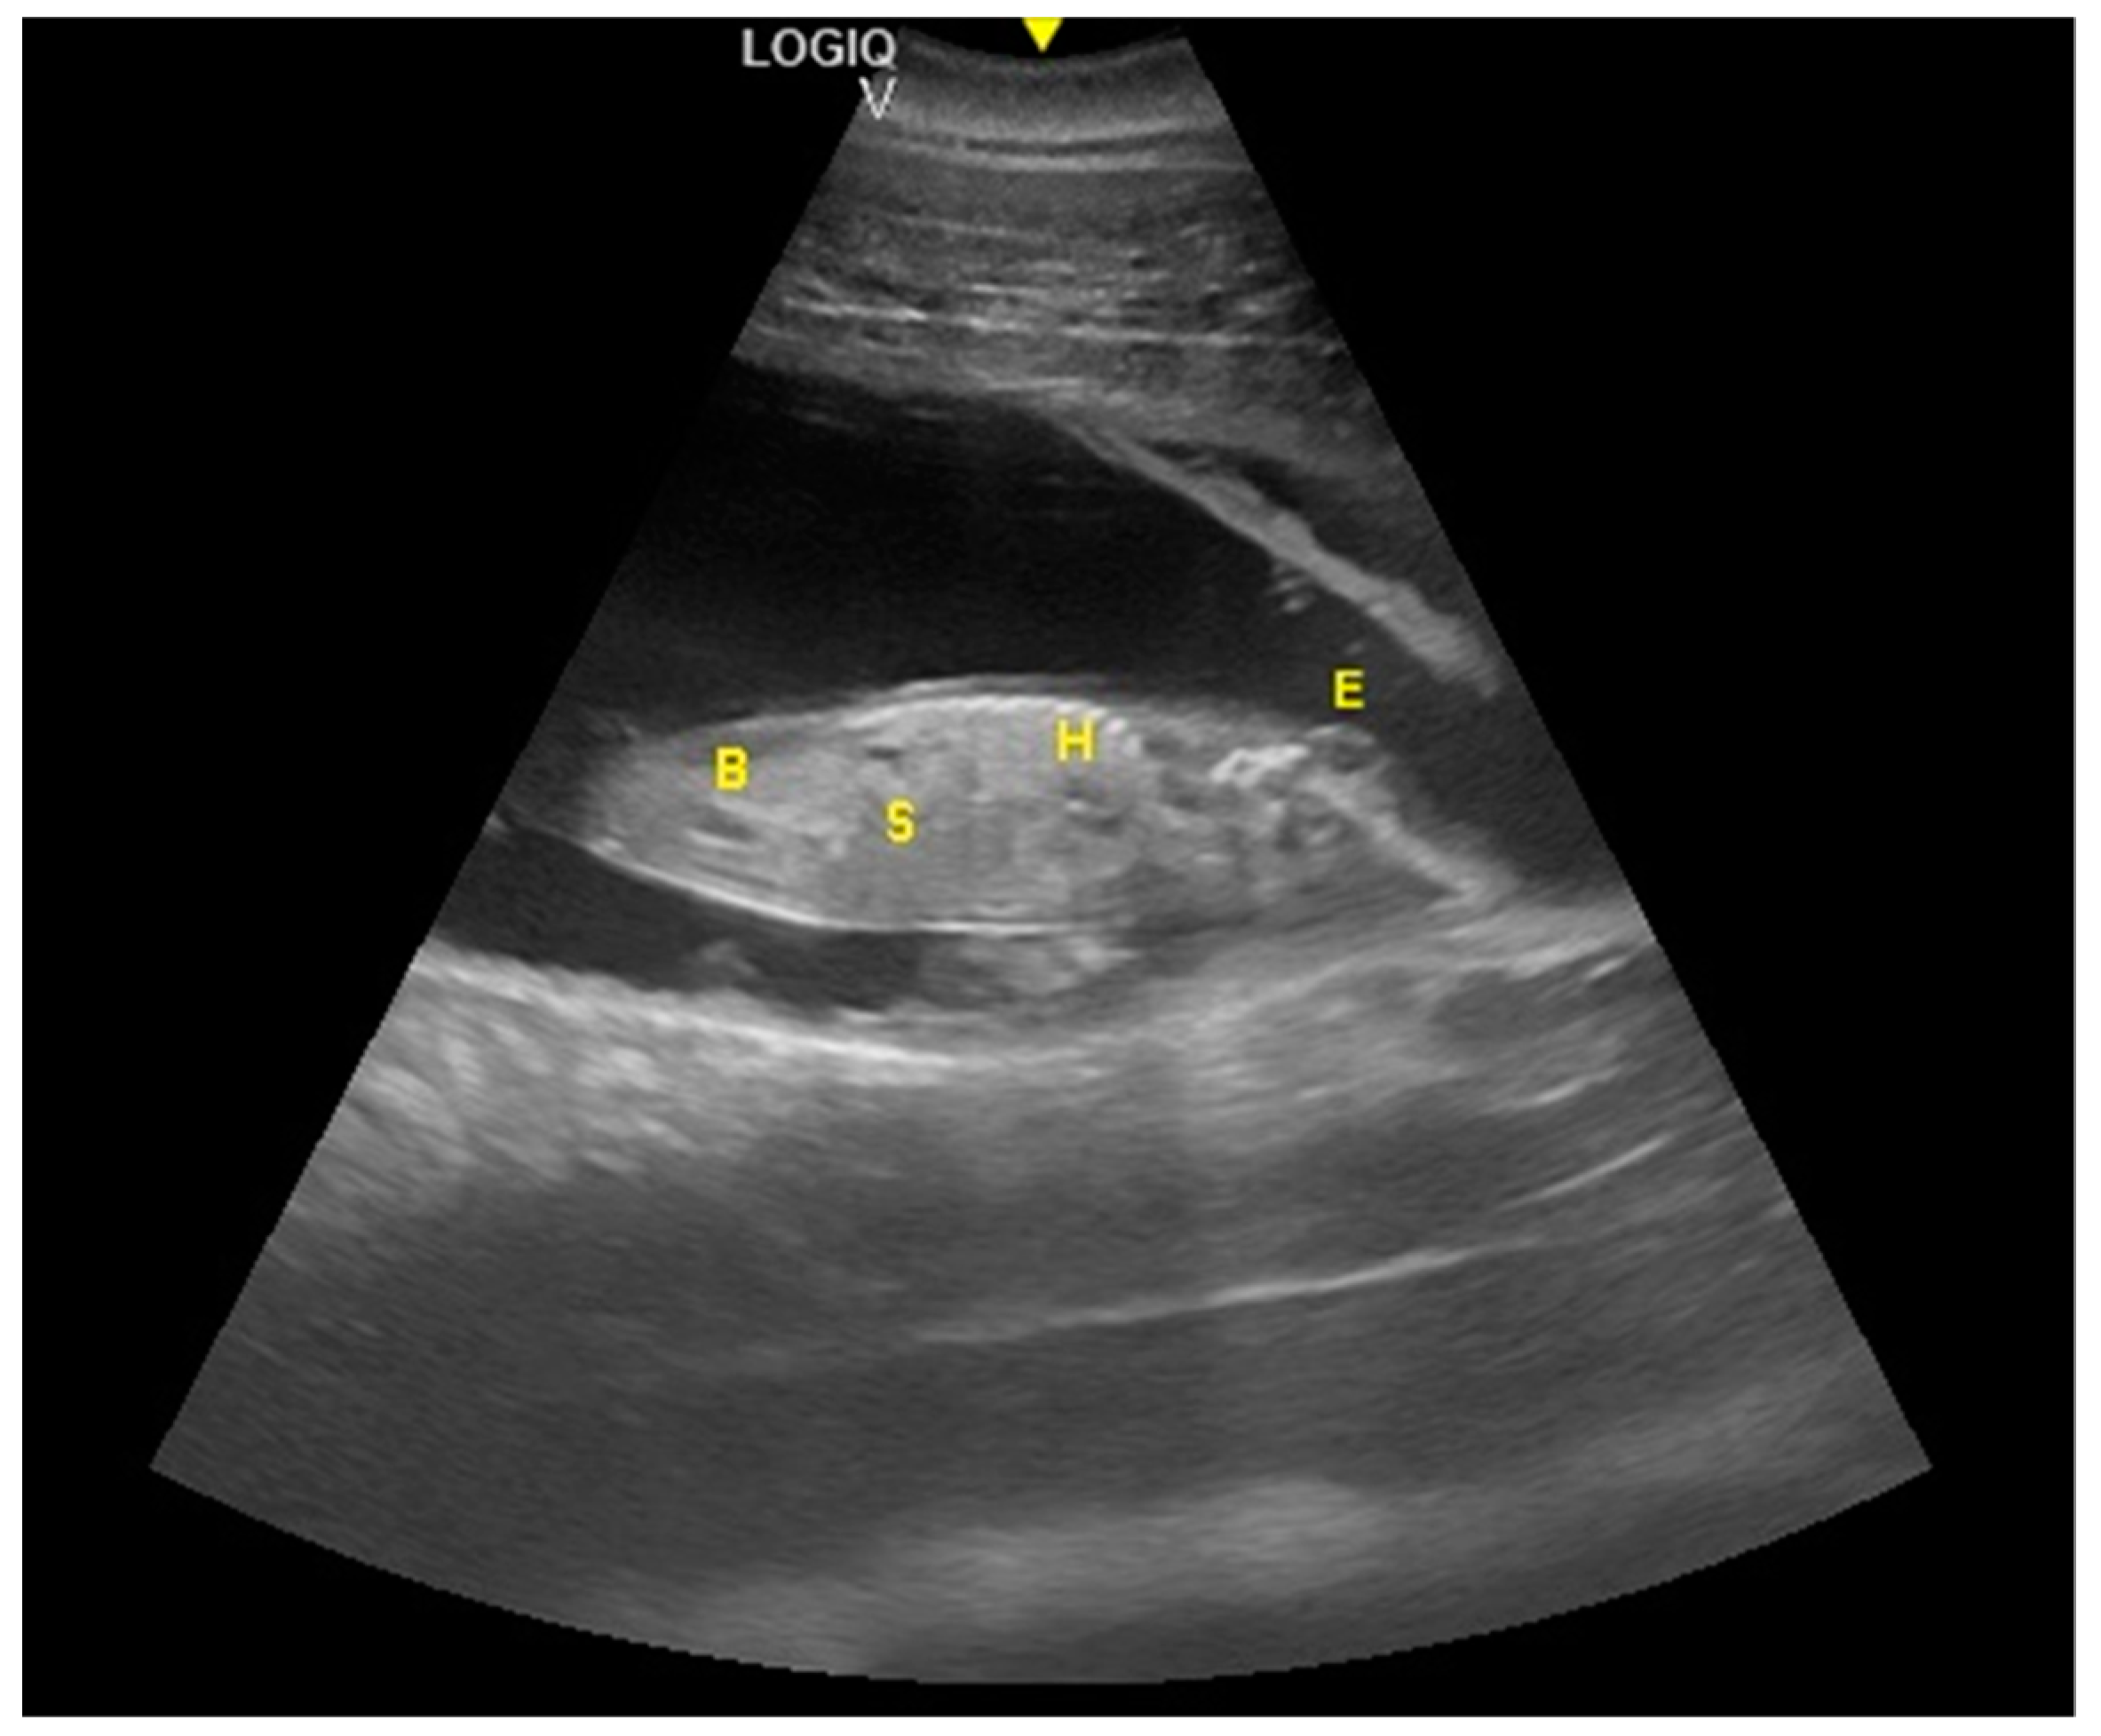

- Ivančič, M.; Gomez, F.M.; Musser, W.B.; Barratclough, A.; Meegan, J.M.; Waitt, S.M.; Llerenas, A.C.; Jensen, E.C.; Smith, C.R. Ultrasonographic findings associated with normal pregnancy and fetal well-being in the bottlenose dolphin (Tursiops truncatus). Vet. Radiol. Ultrasound 2020, 2020, 1–12. [Google Scholar]

- Sklansky, M.; Renner, M.; Clough, P.; Levine, G.; Campbell, M.; Stone, R.; Schmitt, T.; Chang, R.K.; Shannon-Rodriguez, J. Fetal Echocardiographic Evaluation of the Bottlenose Dolphin (Tursiops truncatus). J. Zoo Wildl. Med. 2010, 41, 35–43. [Google Scholar] [CrossRef] [PubMed]